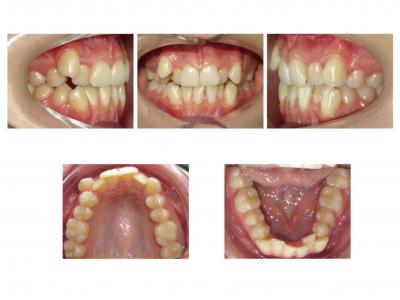

Voici les deux patientes traitées

Ici, dans les deux cas, les deuxièmes prémolaires ont été extraites et les traitements ont duré 18 mois.

Dans le premier cas, la béance s'est fermée spontanément (pas prévu au départ) sans rééducation, sans appareil de contrainte linguale, ni élastique. Il semblerait que le gain de place a permis aux incisives de se redresser spontanément et donc de fermer la béance. La fermeture de la béance, la normalisation de l'environnement anatomique a permis à la langue de se mettre à travailler correctement. Pour le sens transversal, la correction a été aussi spontanée. Juste une minivis dans le secteur 1 a été placée pour recentrer mon milieu (ancrage maximal recherché au départ). Les finitions auraient pu être meilleures. Elle finit avec une légère classe II (on va dire qu’elle est surcorrigée :)). Le traitement a terminé plus tôt que prévu (24 mois annoncé), car problèmes de santé.